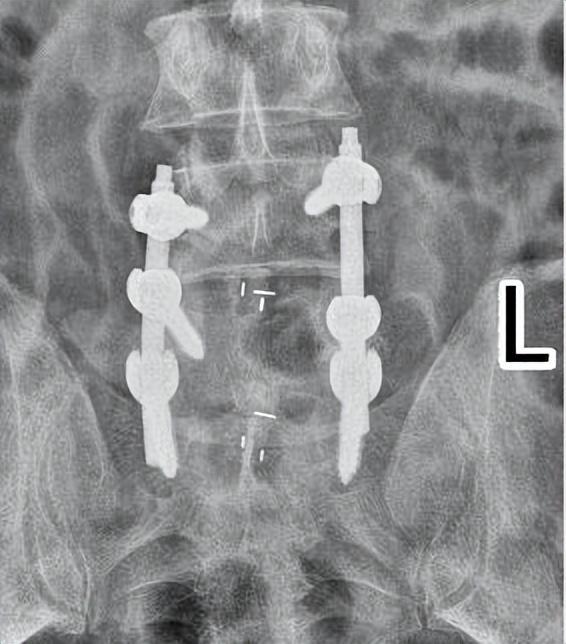

考虑到唐先生病程长、症状重、保守治疗效果差,盛斌主任带领脊柱脊髓损伤专科团队多次讨论后,制定了个体化的手术和康复方案,并于2023年10月27日为其施行腰椎后路椎管扩大减压植骨融合内固定手术。术中,先对L4-5/L5-S1椎板进行切除减压、清除脂肪病灶组织;然后在保证不损伤脊髓和神经的前提下,在显微镜辅助下一点点将压迫的脂肪组织彻底去除,从而直接解除神经压迫,改善症状。

术后,唐先生腰背部疼痛及双下肢麻木的症状明显缓解,术后第10天开始佩戴支具下床锻炼,伤口愈合后,于11月9日顺利出院。

▲术后复查显示:内固定位置良好